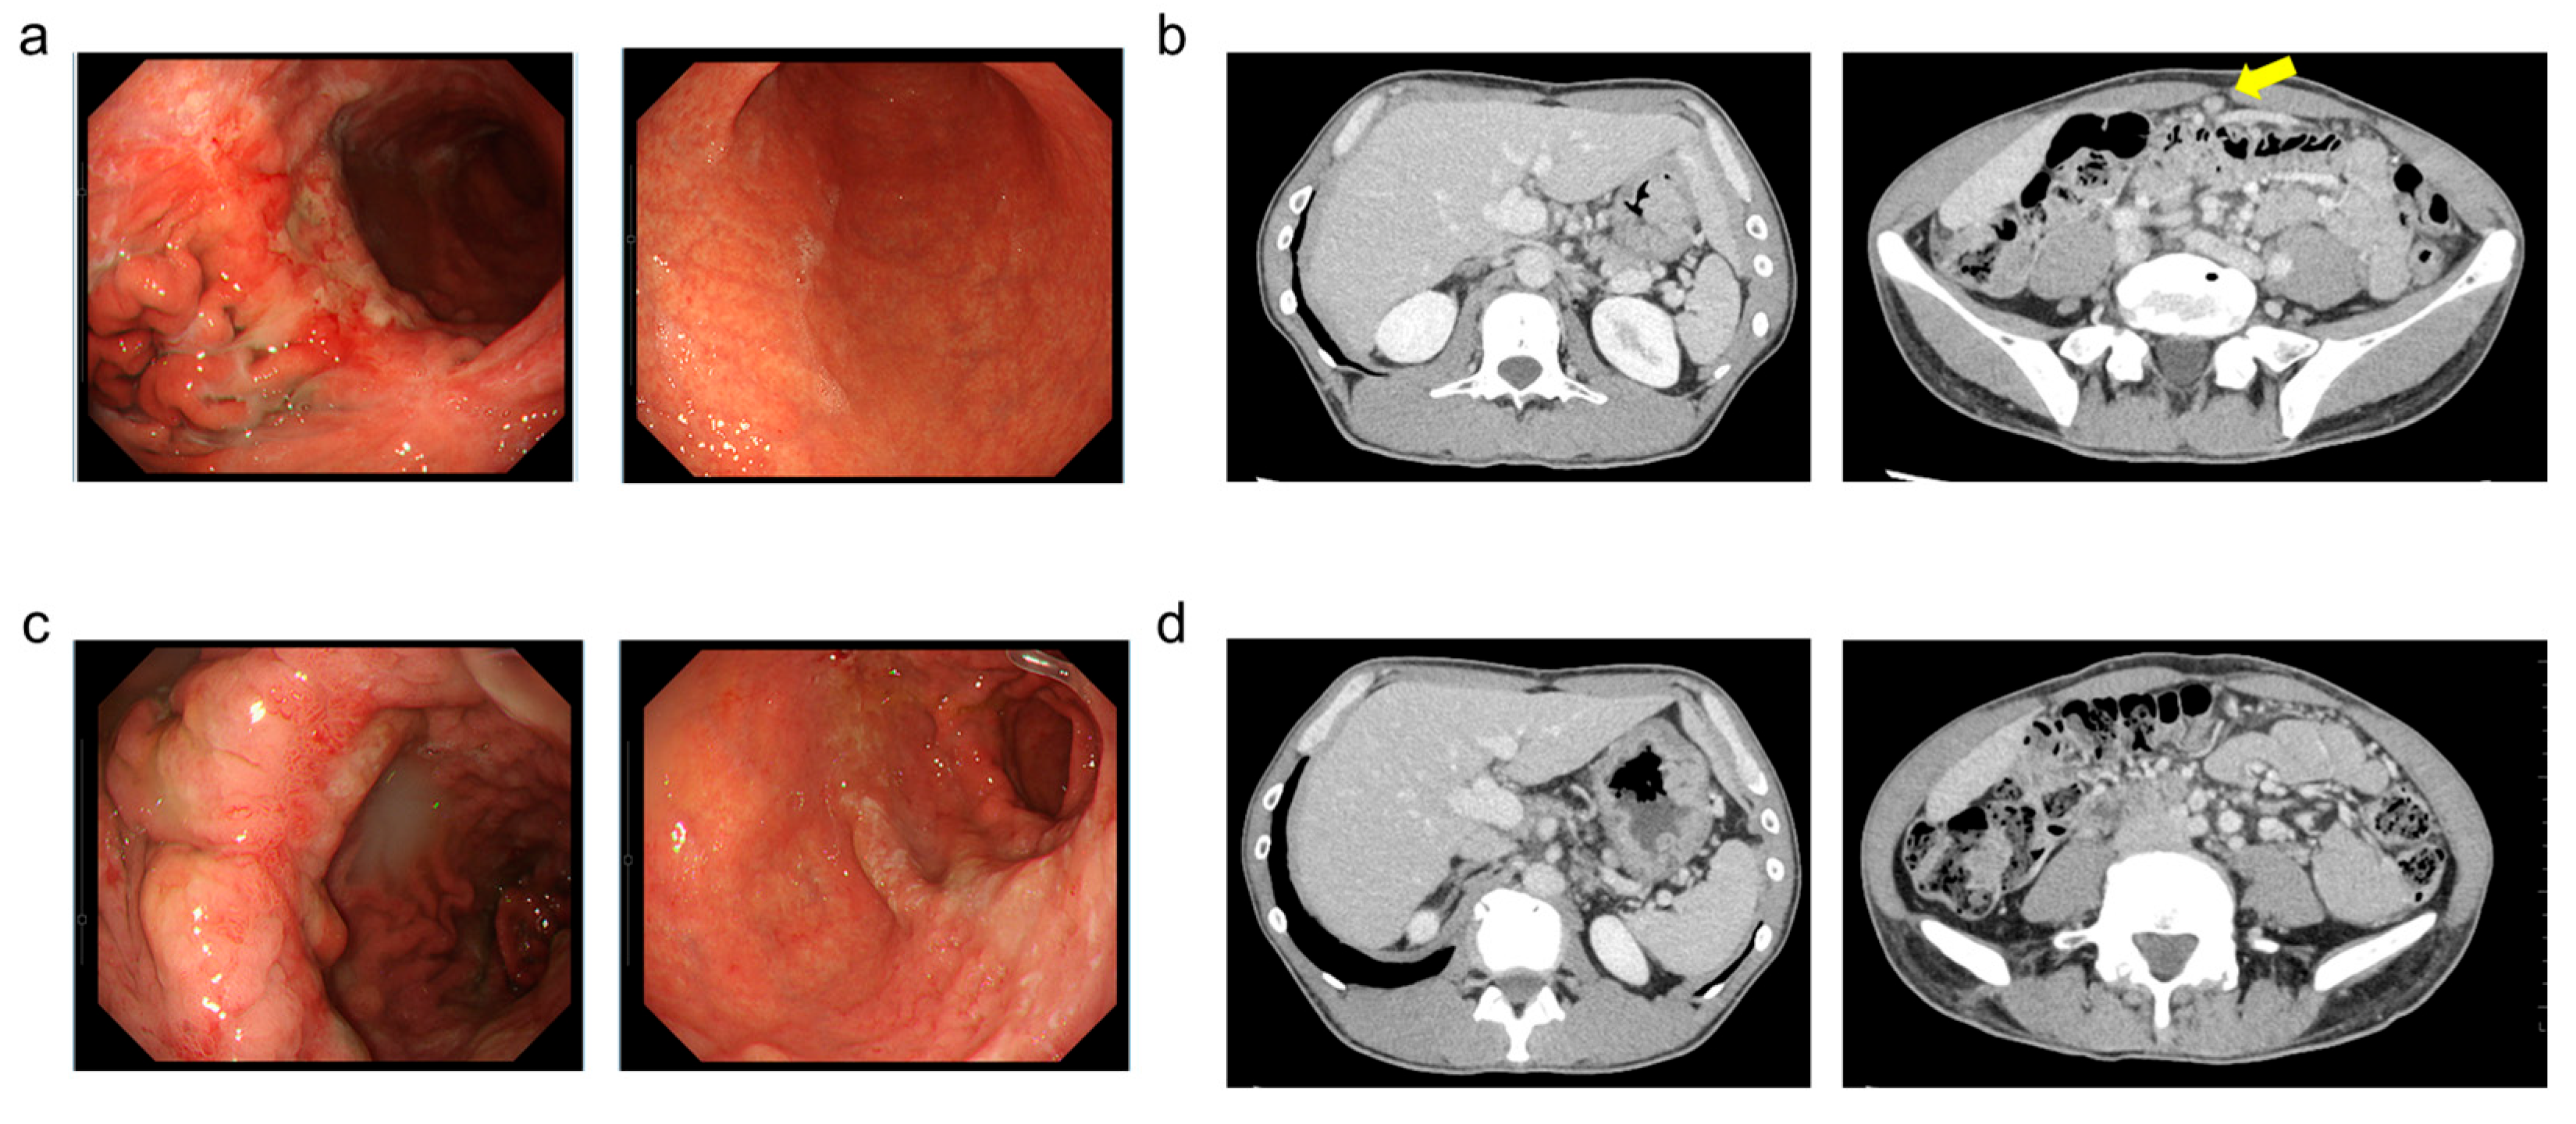

A Mucosal Change like Hypertrophic Gastritis Following Zolbetuximab-Based Therapy in a Conversion Surgery Case of Advanced Gastric Cancer

2. Case Presentation